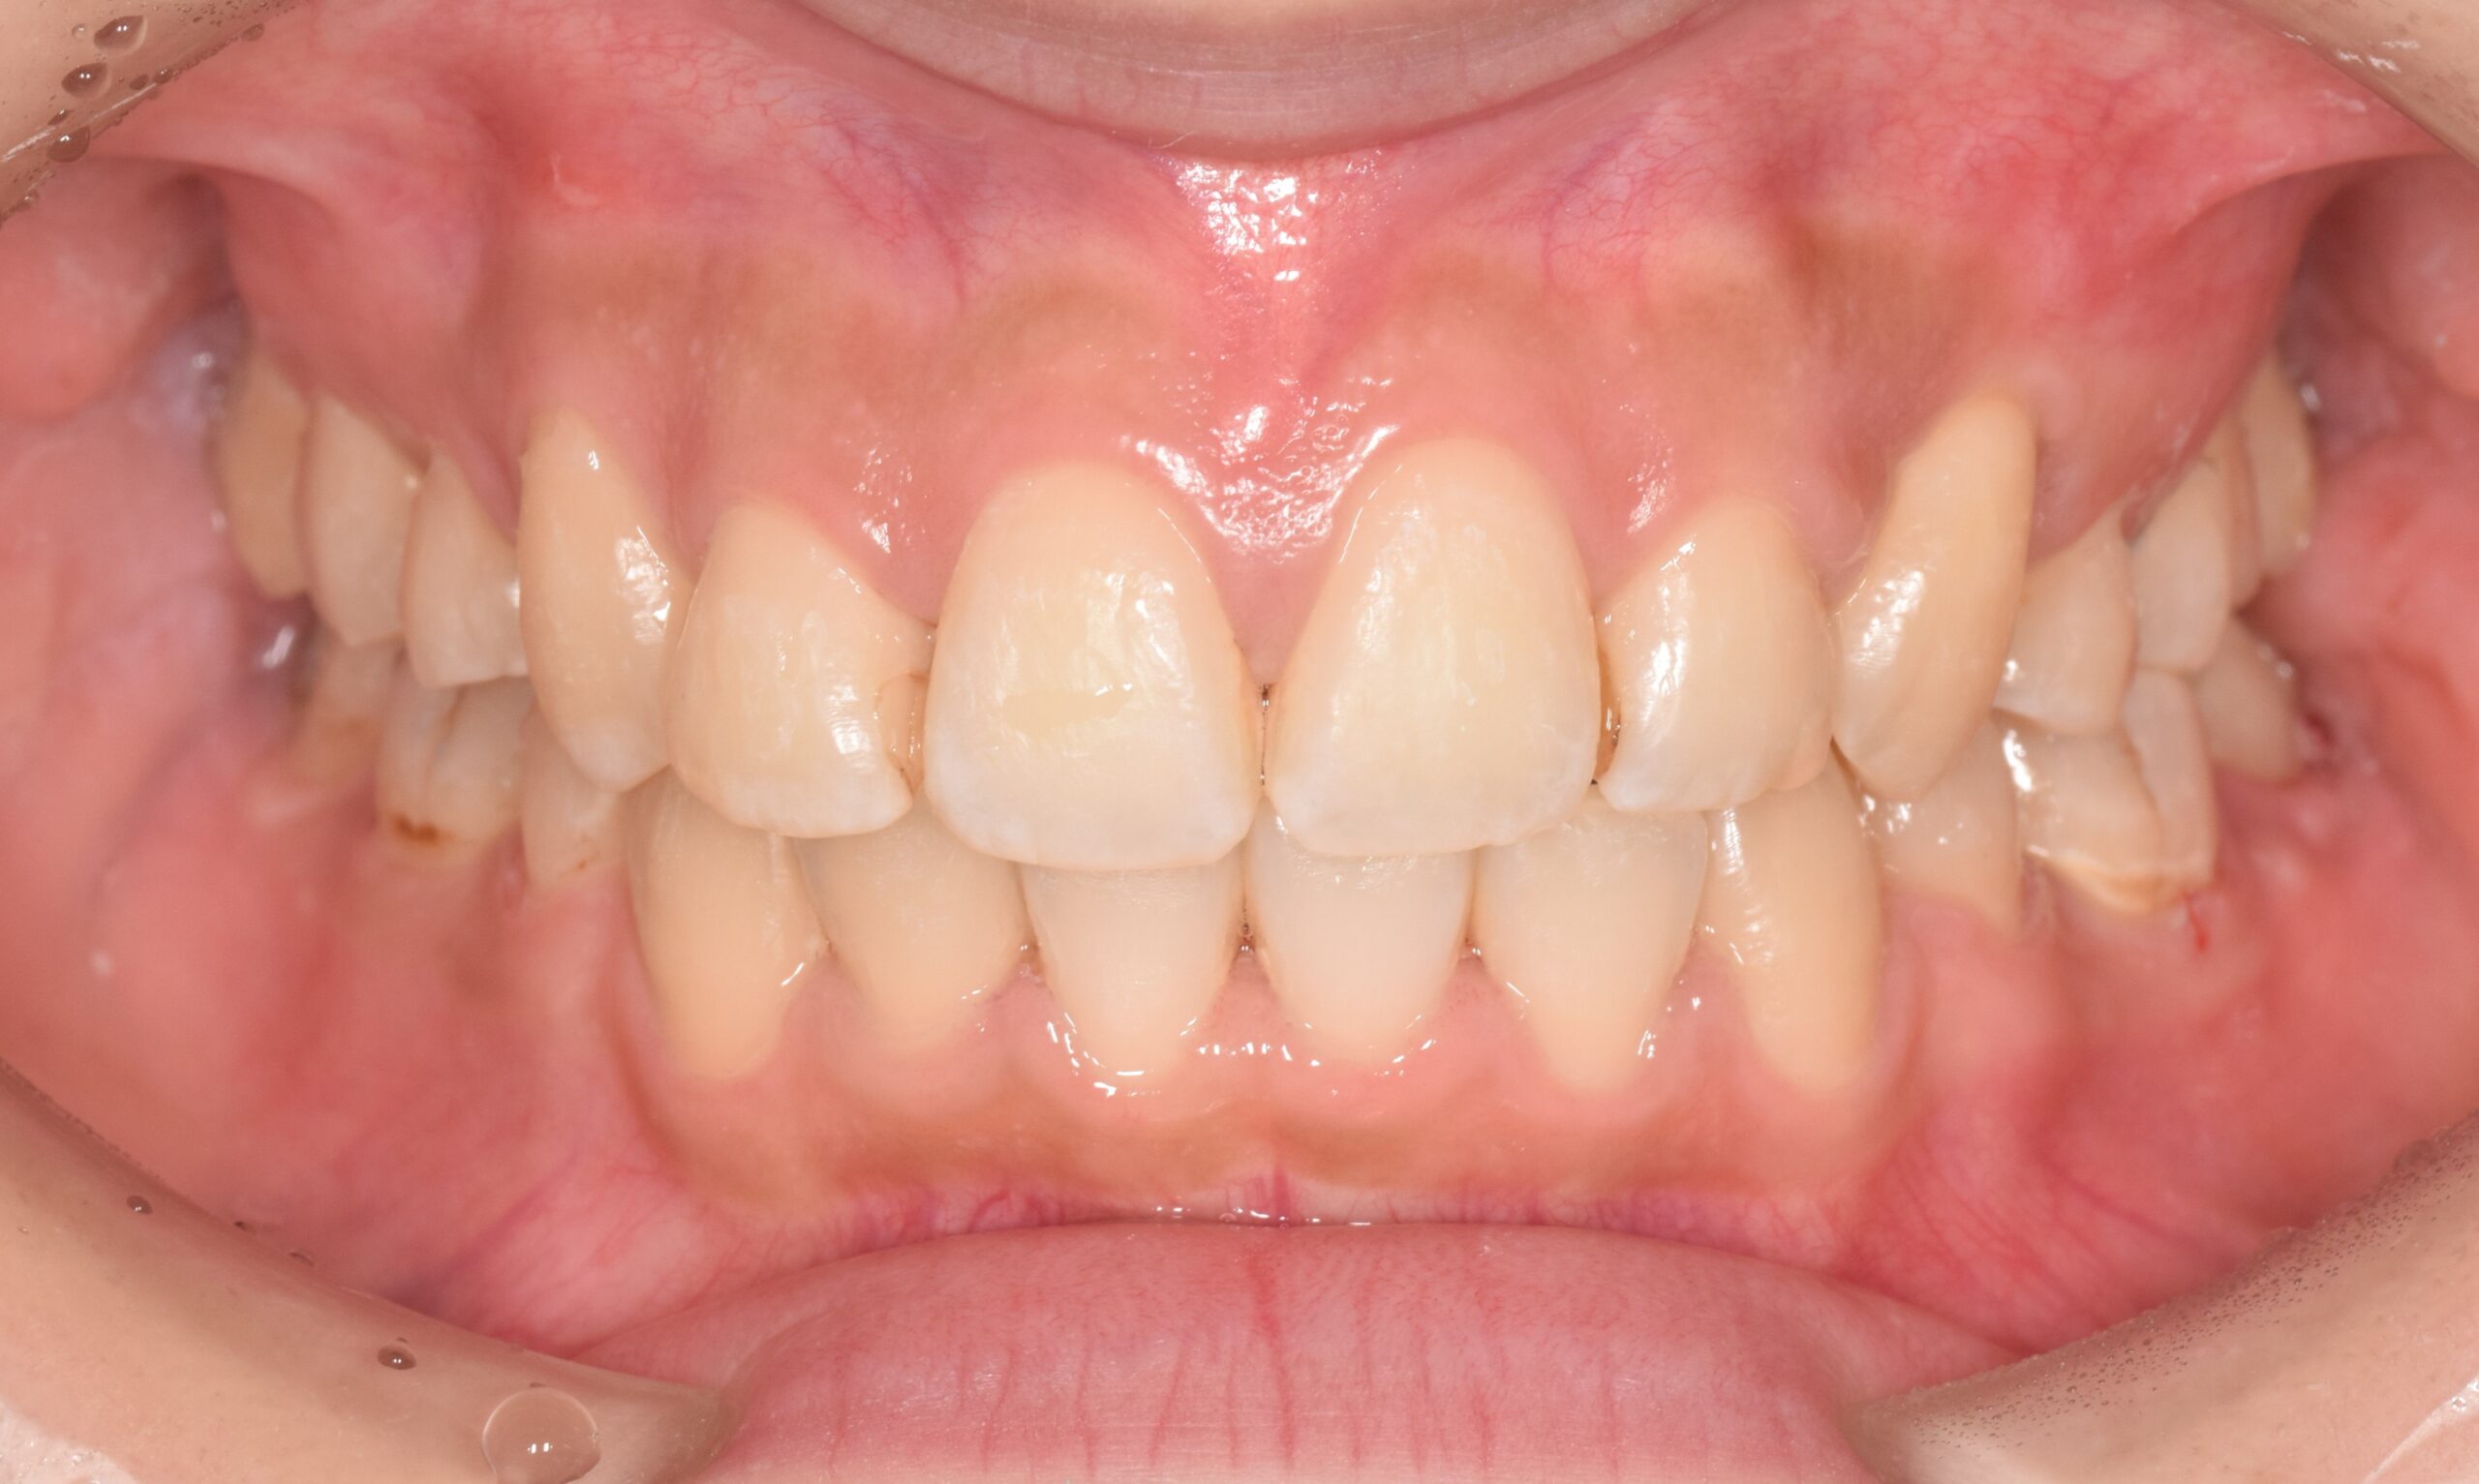

AFTER

| 年齢 | 19歳 |

|---|---|

| 主訴 | ガタガタが気になる |

| 症状 | 過蓋咬合を伴う叢生症例 |

| 治療内容 | 過蓋咬合を伴う叢生症例と診断し上下顎両側第一小臼歯の抜歯を行い、マルチブラケット装置を用いて治療を行いました。上顎は裏側の矯正装置、下顎は表側の矯正装置で治療を行いました。ハーフリンガル矯正治療。 |

| 抜歯部位 | 上下顎両側第一小臼歯 |

| 治療期間 | 3年 |

| 費用(税込) | 1,045,000(税込)別途処置料 |

| 治療のリスク | 虫歯、歯周病の悪化、歯肉退縮、歯根吸収、顎関節症の悪化、後戻り |